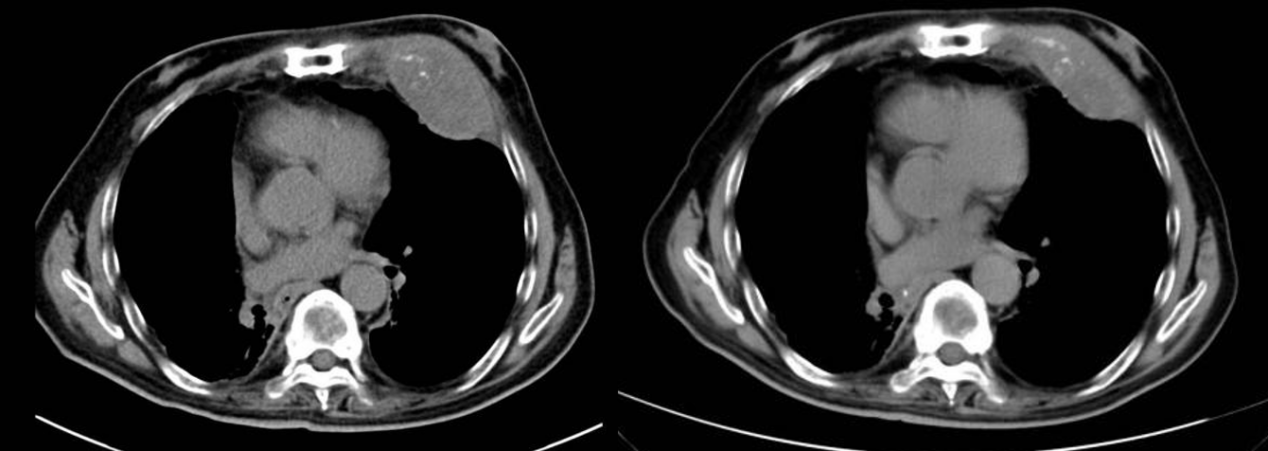

在临床效果方面,接受治疗的患者短期内骨痛即明显减轻,可逐步脱离强效止痛药,翻身、行走等日常活动能力恢复。治疗前后的CT影像对比显示,病灶及周围软组织肿物范围显著缩小,骨质破坏进展得到有效遏制,癌细胞活性明显下降。此外,该治疗方式便捷性突出,患者仅需住院2至3天即可完成治疗,全程无明显不良反应,术后无放射源残留,治疗结束当天即可恢复正常生活,且治疗费用相对较低。

患者1治疗前后图像